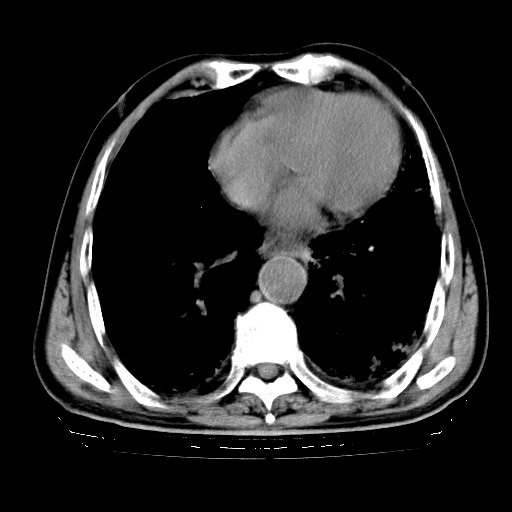

标题: CT25149:男,69岁,反复咳嗽、咳痰五年余,呼吸困难三天。 [打印本页]

男,69岁,反复咳嗽、咳痰五年余,呼吸困难三天。

慢支伴感染、肺气肿、肺心病

慢支伴感染、肺气肿、肺心病!支持!另:间质纤维化!

慢支伴感染、肺气肿、肺心病。双肺间质性改变(间质纤维化)。